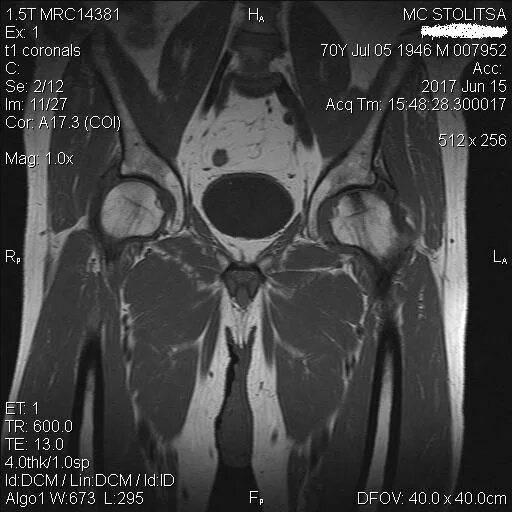

Мрт тазобедренного сустава в минске